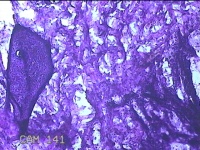

左前臂结节

性别

女

年龄

46岁

临床诊断

皮脂腺囊肿

一般病史

发现左前臂结节4个月余,无明显疼痛及不适。

标本名称

大体所见

灰白暗红色组织1.3x0.8x0.3cm一块,表面带梭形皮肤1.2x0.3cm,皮下见结节1x0.8x0.3cm一个,切开结节呈实性,切面灰白粉红色,质软。